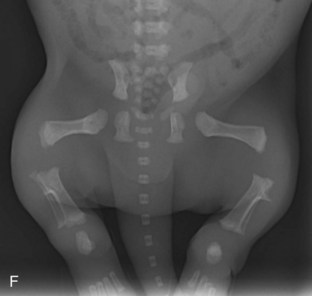

Y para muestra, un botón. En esta tabla te ponemos los tiempos de cierre de las placas de crecimiento de un cachorro:

| HUESO | CIERRE PLACA DE CRECIMIENTO |

|---|---|

| Húmero (a la altura de la escápula) | 10-12 meses |

| Radio (a la altura del codo) | 9-11 meses |

| Huesos de los dedos | 6-7 meses |

| Huesos de la pelvis | 5-6 meses |

| Fémur (a la altura de la cadera) | 9-11 meses |

| Tibia (a la altura de la rodilla) | 10-14 meses |

Y aquí te ilustramos de lo que estamos hablando con varias radiografías de cachorros en las que puedes ver perfectamente que los huesos parecen «flotar» en el espacio: